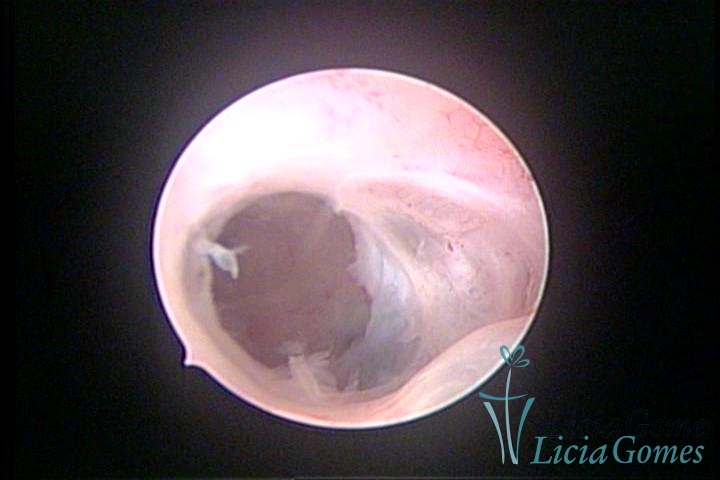

• SINÉQUIA TIPO FIBROSA